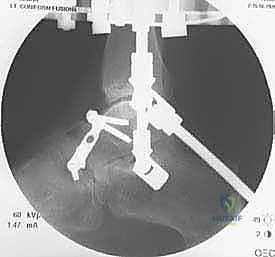

تُجرى عملية تشتيت مفصل الكاحل تحت التخدير النصفي أو الكلي، وتستغرق عادة من ساعتين إلى ثلاث ساعات. هذه الخطوات تعكس البراعة الجراحية التي يتمتع بها الأستاذ الدكتور محمد هطيف:

يتم تمرير أسلاك معدنية رفيعة جداً (Kirschner wires) ومسامير نصفية (Half-pins) عبر العظام لتثبيت الحلقات. يعتمد الأستاذ الدكتور محمد هطيف على معرفته التشريحية العميقة واستخدام جهاز الأشعة المرئي (C-arm) لضمان مرور هذه الأسلاك في "الممرات الآمنة" (Safe corridors) بعيداً عن الشرايين والأعصاب الحيوية.

الخطوة الرابعة: تركيب المفاصل الصناعية (Hinges)

هنا يكمن السر الأكبر للنجاح. يتم توصيل حلقة الساق بحلقة القدم باستخدام مفاصل معدنية قابلة للحركة (Hinges). يجب أن يتم وضع محور هذه المفاصل المعدنية ليتطابق تماماً مع المحور التشريحي الطبيعي لدوران مفصل الكاحل (Center of Rotation of the Talus). هذه الدقة تضمن إمكانية تحريك الكاحل أثناء فترة العلاج دون إحداث ضغط غير متساوٍ على الغضروف.

الخطوة الخامسة: تطبيق التشتيت (Distraction)

أثناء العملية، يقوم الدكتور هطيف بإبعاد حلقة الساق عن حلقة القدم تدريجياً وببطء باستخدام قضبان ملولبة، حتى يصل إلى مسافة تشتيت تبلغ حوالي 5 إلى 6 ملليمترات. يتم التأكد من هذه المسافة عبر الأشعة السينية داخل غرفة العمليات.